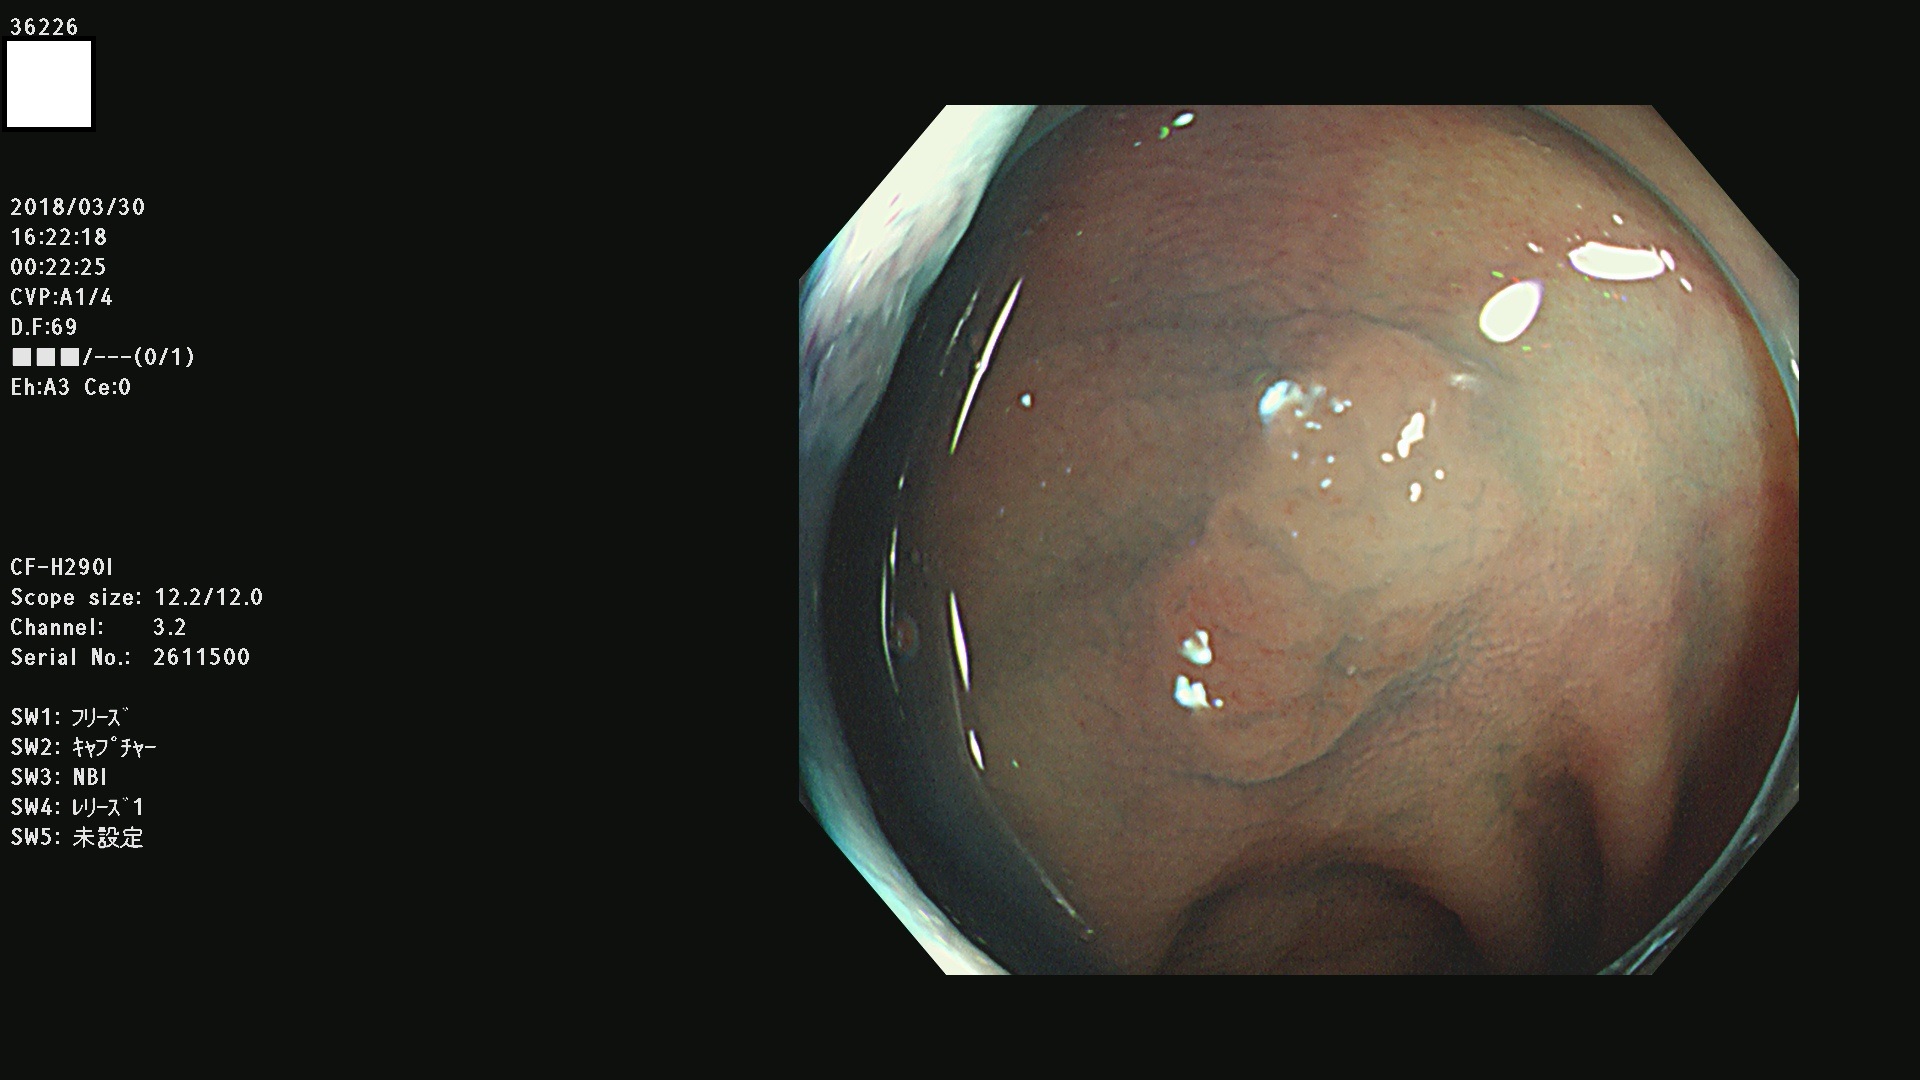

36201 36202 36203 36205 36207 36209 36210 36212 36213 36214 36215 36217 36220 36221 36222 36224 36225 36226 36227 36229 36230 36231 36232 36235 36236 36238 36240 36243 36244 36246 36247(SSAPのみ。SPS) 36248 36249 36251 36252 36253 36254 36255 36256 36257 36258 36259 36261 36262 36264 36265 36267 36269 36270 36272 36274 36275 36276 36279 36280 36281 36283 36285 36288 36289 36291 36292 36295 36296 36297 36299

発見困難で危険性の高い平坦型病変(上記100名より抽出)